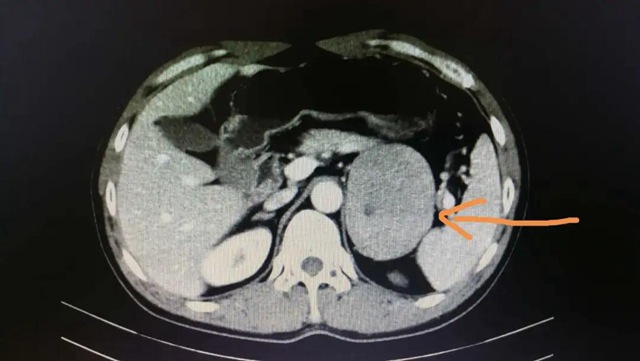

該患者,男性,52歲,因“尿頻2年”住院,檢查發現左側腎上腺腫瘤(9cm)。

▲CT掃描下的腎上腺腫瘤